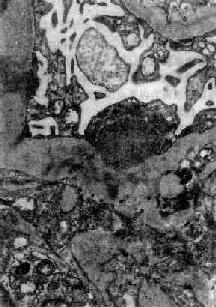

在电子显微镜下可见肾小球系膜细胞和内皮细胞增生肿胀。基底膜和脏层上皮细胞间有致密物质沉积。这些沉积物大小不等,有的很大,在基底膜表面呈驼峰状或小丘状(图12-8,图12-9)。沉积物表面的上皮细胞足突多消失。基底膜变化不明显有时边缘稍不规则。沉积物一般在发病后几天就可出现,在4~6周内消失。有时基底膜内侧内皮细胞下和系膜内也可见小型沉积物。

图12-8 毛细血管内增生性肾小球肾炎

电镜下见肾小球毛细血管基底膜表面上皮细胞下有多数驼峰状电子致密沉积物

图12-9 毛细血管内增生性肾小球肾炎

电镜下见驼峰状沉积物位于毛细血管基底膜表面。沉积物表面有上皮细胞覆盖,上皮细胞足突消失